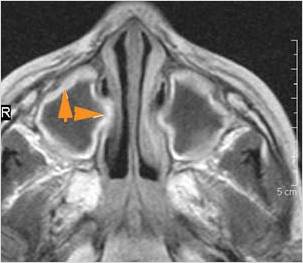

The anterior ethmoid arteries are on a mesentery.